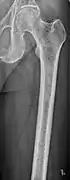

Medical imaging

The diagnostic examination of a person with suspected multiple myeloma typically includes a skeletal survey. This is a series of X-rays of the skull, axial skeleton, and proximal long bones. Myeloma activity sometimes appears as "lytic lesions" (with local disappearance of normal bone due to resorption). And on the skull X-ray as "punched-out lesions" (pepper-pot skull). Lesions may also be sclerotic, which is seen as radiodense.[47] Overall, the radiodensity of myeloma is between −30 and 120 Hounsfield units (HU).[48] Magnetic resonance imaging is more sensitive than simple X-rays in the detection of lytic lesions, and may supersede a skeletal survey, especially when vertebral disease is suspected. Occasionally, a CT scan is performed to measure the size of soft-tissue plasmacytomas. Bone scans are typically not of any additional value in the workup of people with myeloma (no new bone formation; lytic lesions not well visualized on bone scan).